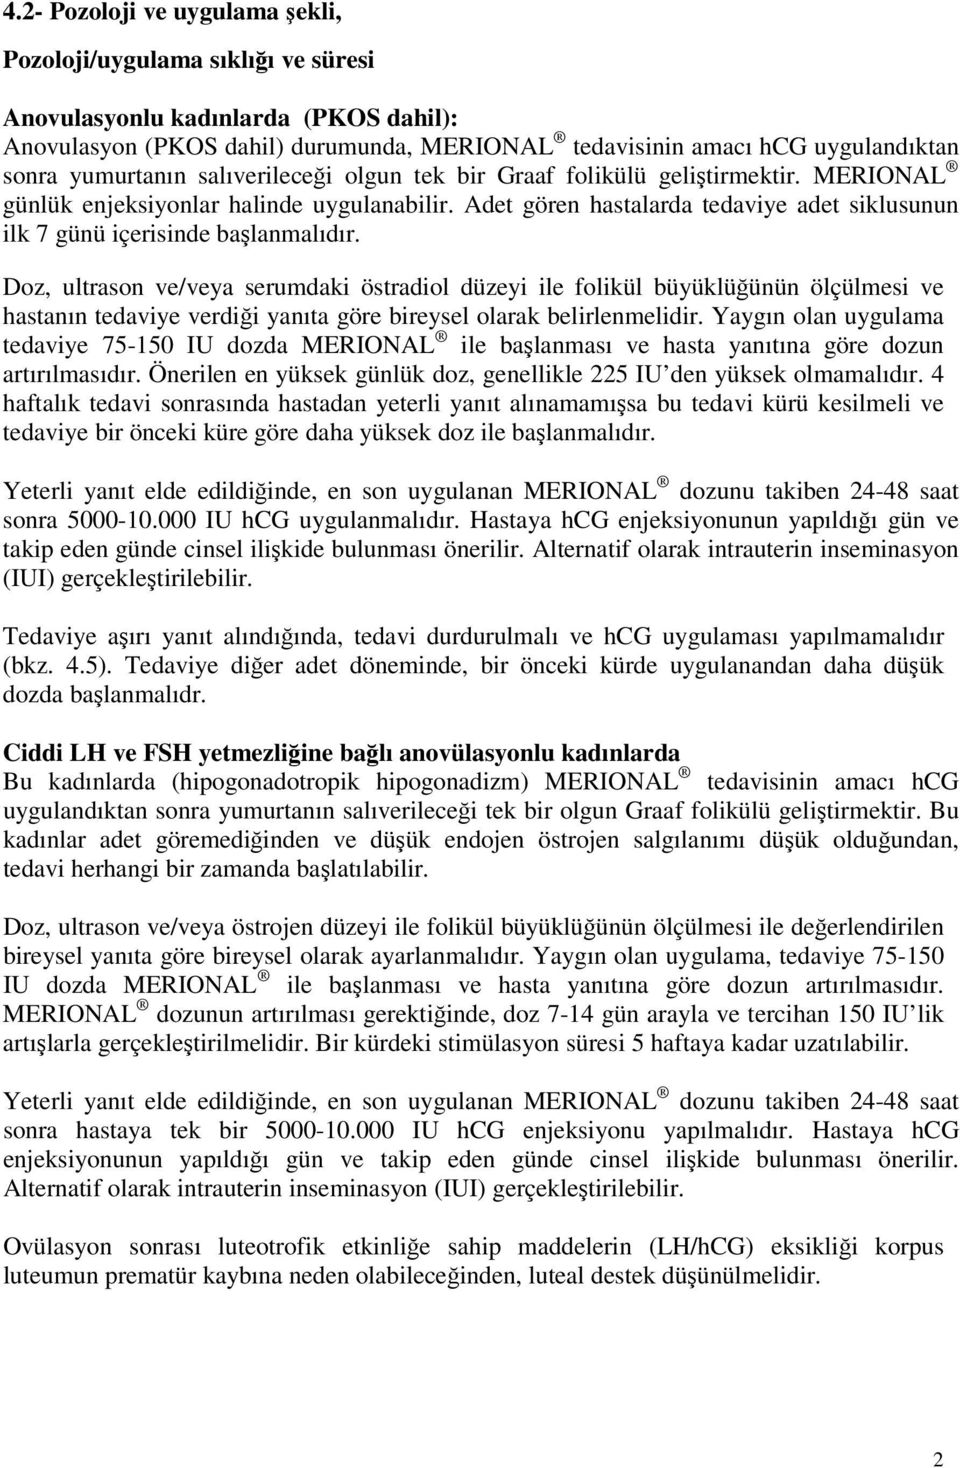

Tüp bebek tedavilerinde hedeflenen nokta istenilen sayıda ve istenilen kalitede embriyo elde etmektir. Tüp bebek tedavisinde amaç. Tüp bebek kadına veya erkeğe bağlı kısırlık sebebiyle çocuk sahibi olamayan anne baba adaylarına uygulanan yardımcı üreme tekniğine verilen addır. Yumurtalıklar hap serophene gonaphene klomid klomen veya gonadotropin gonal f puregon menogon menopur fostimon merional adı verilen iğneler ile uyarılabilir.